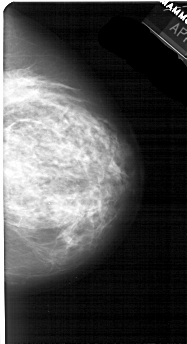

A_1766_1.RIGHT_MLO